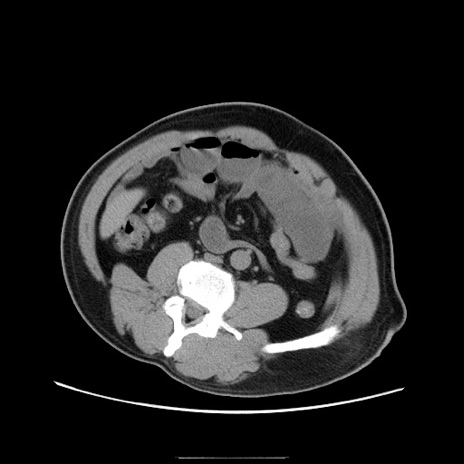

症例22(横断像)

【症例】50歳代男性

【主訴】腹痛

【現病歴】AVMからの被殻出血のため回復期リハ病棟入院中。 本日午後3時頃急に下腹部痛が出現した。

【既往歴】AVM、被殻出血、虫垂炎、高血圧

【身体所見】意識晴明、左半身不全麻痺、会話の理解は良好、36.5°C、腹部:膨隆、全体に板状硬、下腹部正中に圧痛点あり、反跳痛-、筋性防御不明、右下腹部にope scar

【データ】WBC 9400、CRP 0.06